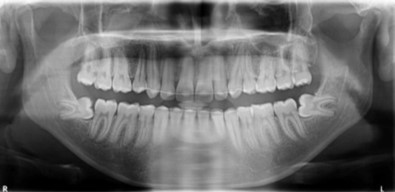

Radiographic assessment. The panoramic radiograph confirmed the presence of all permanent teeth with the presence of 18, 28, 38 and 48 tooth germs with normal alveolar bone levels. (Figure 2).

Figure 2.Pre-treatment panoramic radiograph